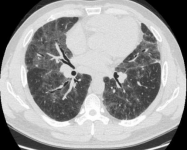

病例:男性,33岁,劳力性呼吸困难4年,加重3月,在治疗之前,我们看到的影像有些磨玻璃影、马赛克征,还有小叶中央型结节,并进行了外科肺活检。患者在从事铸造工作过程中间断接触异氰酸酯。停止工作暴露,并糖皮质激素经过治疗后,病情好转,但停用激素后又出现了肺部弥漫的磨玻璃影,肺功能也有所下降。

图:(从左至右)治疗前、脱离暴露+激素治疗10月、停激素18月